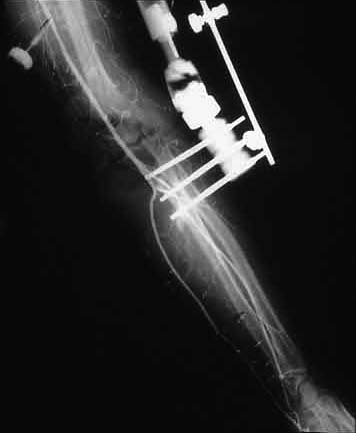

Case 2 - avulsed elbow joint with complete pulling apart of brachial artery, open wound with huge overlying skin loss. Immediate OR, brachial artery shunted, THEN Ortho puts on cross-joint ex-fix, we come back and definitively repair artery (ASVG), document patency with on table completion angio--then plastics swings lat dorsi pedicled flap thru axilla to cover.

Shunt then ex-fix

Vascular repair